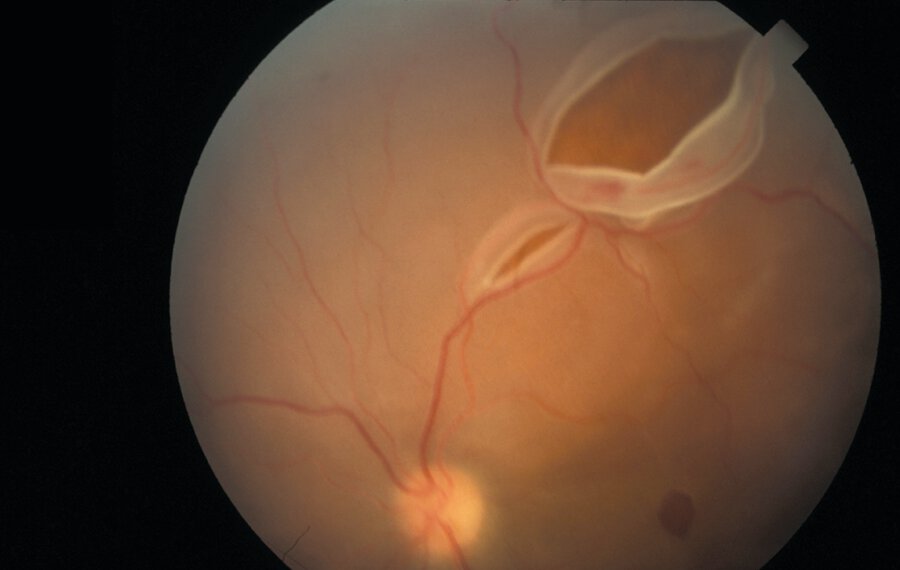

A 68-year-old woman is evaluated for reduced vision and flashing lights in her left eye that began this morning. This was preceded by floaters in her left eye, first appearing several days ago and now with increasing frequency. She has no other symptoms. Medical history is significant for myopia. She takes no medications.

On physical examination, she has an inferior visual field defect in her left eye. Visual fields in the right eye are normal. Pupils are equally round and reactive to light and accommodation. Visual acuity is 20/60 in the left eye and 20/20 in the right eye. Nondilated funduscopic examination is normal.

Retinal detachment - painless visual field defect. Risk factors include age, myopia, and recent cataract surgery.

Urgent opthamology evaluation -